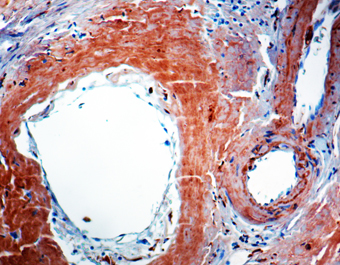

IHC-P analysis of human amyloidosis tissue using GTX27501 beta Amyloid (1-40) antibody [BAM-10].